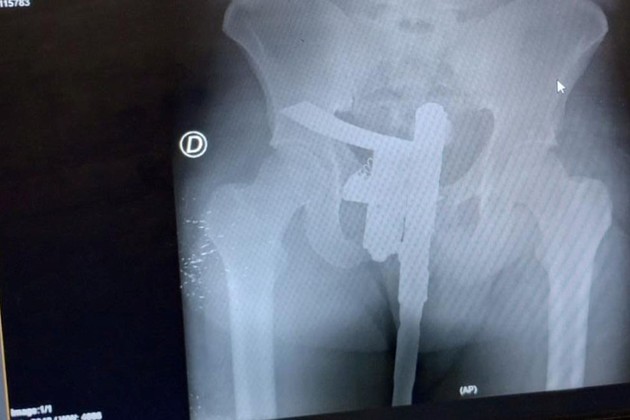

Como es de rutina un médico hizo una primera evaluación y, como el paciente manifestaba dolor en la zona de la cadera, se ordenó realizar una placa radiográfica.

El estudio se concretó de manera normal, aunque minutos después el revelado permitió descubrir una "sorpresa". En la placa se observó que el paciente tenía un arma de fuego oculta entre sus genitales.